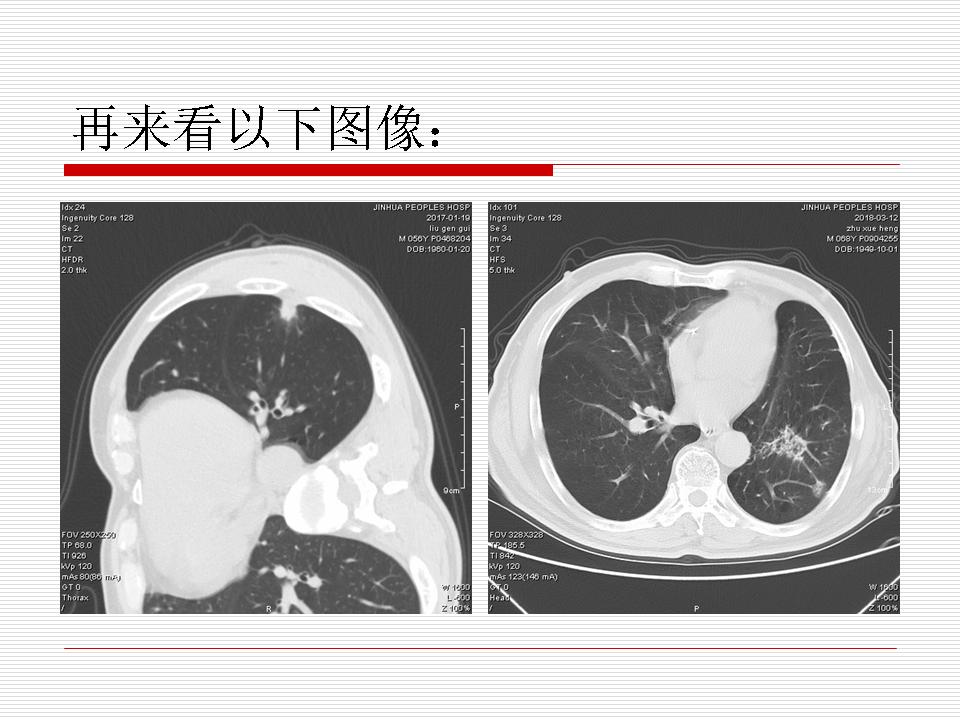

肺部阴影永恒且最重需要鉴别的是:到底是炎症还是肿瘤?但临床的病例中的影像表现难以界定或有些肿瘤特征,同时又有些炎症特点是非常常见的情况。作为临床医生我们怎么去总结分析,并找到之所以是炎症或之所以是肿瘤的细微差别或特点非常重要,也非常有用。2019.12.7浙江省2019年胸心外科学学术年会在宁波召开时,我的临床病例分析与经验总结<那些像肺癌的炎症与像炎症的肺癌>获得在大会交流的机会,以下为该PPT的内容,与你分享,希望对同道有益,有借鉴与启迪。若有探讨与进一不完善的建议,欢迎文末留言讨论: